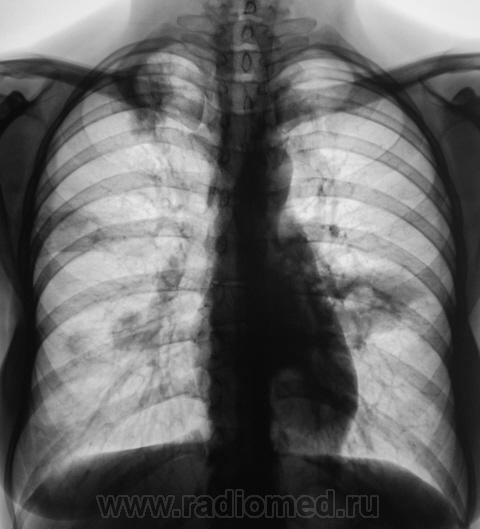

4. Это снимки одной из дочерей «тетки», у которой, как и у всякой любвиобильной дамы есть и ребеночек.

5. «Девица красавица» была дообследована соглано минимальному стандарту – томография. Микроскопия, тоже не подкачала. Пациентка была направлена в областную туббольницу, где было начато интенсивное специфическое лечение.